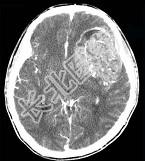

- 单项选择题男,15岁, 进行性头痛1年余,CT检查如图所示, 最可能的诊断是 ( )